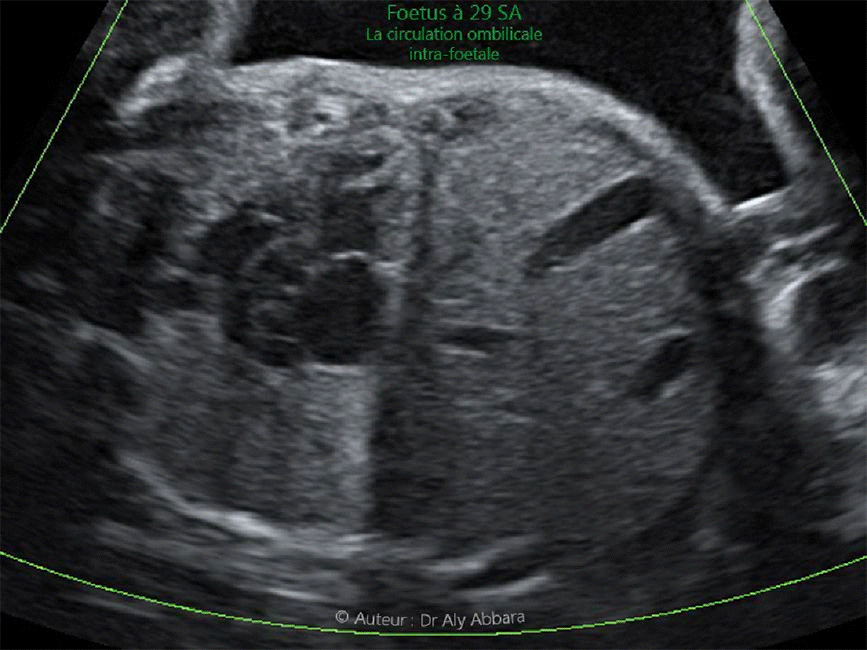

Aspect échographique de l'insertion du cordon ombilical sur la paroi abdominale foetale

Trajet et état de circulation de la veine ombilicale in utero

Images échographiques réalisées à 29 SA montrant un cordon ombilical d'aspect normal au niveau de son insertion au pôle fœtal et également montre la normalité de la circulation ombilicale intra-foetale.

Ce foetus qui ne présente pas d'anomalie morphologique ou biométrique à 29 SA sera la victime d'une mort fœtale in utero à 37 SA, avec une seule étiologie retrouvée : sténose et torsion du cordon ombilical à son extrémité fœtale.